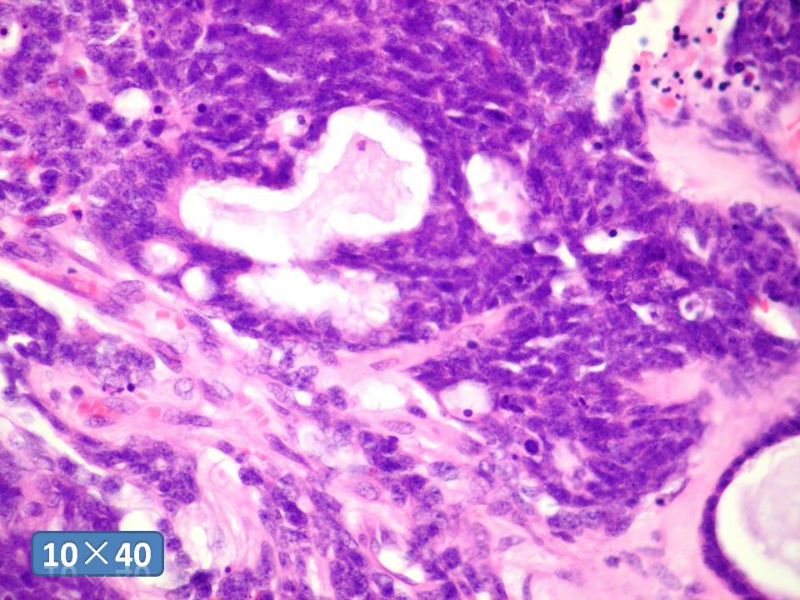

男性,49岁,间断左鼻腔出血3个月。

标签:是嗅母么?

1)嗅神经母细胞瘤?

2)腺肌上皮癌?

3)肌上皮癌?

4)神经内分泌癌?

5)腺样囊性癌?

6)其他?

腺肌上皮癌

感觉要排除畸胎癌肉瘤。

间质为恶性梭形细胞成分,其间感觉是腺体,两种成分密切相关....

免疫组化S-100的阳性区域方式...嗅母可能性大。

支持嗅神经母细胞瘤(伴有腺体分化)

嗅神经母细胞瘤

有上皮和间叶2种结构,畸胎性癌肉瘤是要考虑一下的吧!